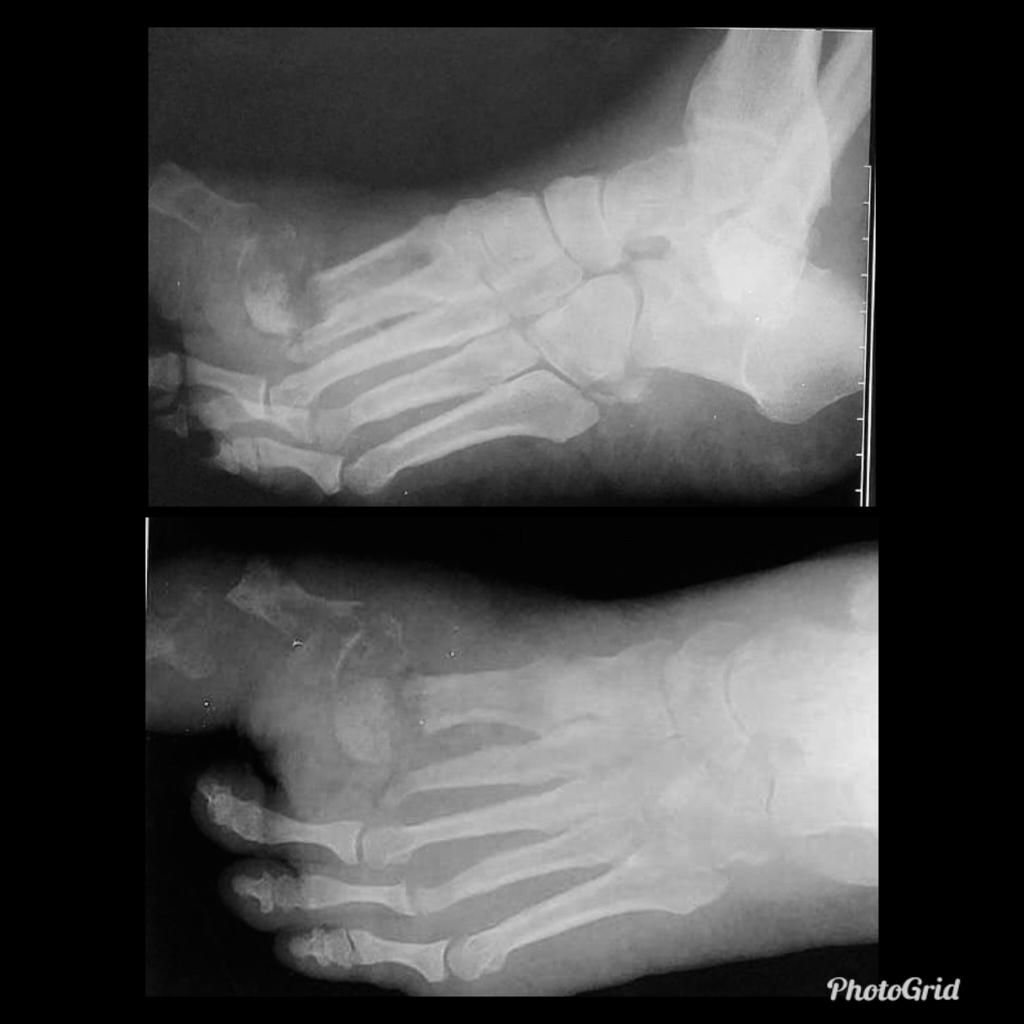

In the presented case there are destruction of talar head and neck with dislocation of talo-navicular joint, resorption of midfoot bones, subchondral sclerosis and multiple subchondral cysts on talocalcaneal aspect and cuboid facet of the calcaneum, progressive decrease of calcaneal inclination with typical rocker-bottom deformity, soft tissue swelling and arterial calcification. Bony debris are seen on dorsal aspect of the foot and posterior ankle joint. All findings are suggestive of Charcot neuro-osteoarthopathy, which is primarily an articular disease and most commonly located in the midfoot.

Osteomyelitis in diabetic foot is infection of the bone that 90% are results from contiguous spread of a skin ulcer. Consequently, the most common location for osteomyelitis is at the pressure points of the forefoot (metatarsal heads, IP joints) and in the hindfoot at the plantar aspect of the posterior calcaneus. Classic triad of osteomyelitis in plain radiograpy are lucencies, periosteal reaction, and bony destruction.

Unlike osteomyelitis, Charcot neuroarthropathy is primarily an articular disease and not related to overlying skin or soft tissue changes. Charcot neuroarthropathy commonly involves multiple midfoot bones. Features include joint instability, dislocation, destruction, disorganization, increased bone density, joint debris and deformity. Presence of subchondral cysts and intraarticular bodies with absence of the secondary signs for osteomyelitis support neuroarthropathy without infection.

In the early stage radiography will not demonstrate bone abnormalities, but MRI will show subchondral bone marrow edema. The subcutaneous soft tissues are not typically involved in Charcot arthropathy.

Osteomyelitis in chronic Charcot is usually located in the midfoot, while osteomyelitis in diabetic neuropathy without Charcot is usually in the forefoot and hindfoot.

Diabetic foot remains a challenge for the clinicians due to confusing clinical picture and associated complications. It may present as neuroarthropathy, septic arthritis, osteomyelitis, ischemic devitalised bone or as soft tissue complications such as cellulitis, myositis, ulceration, callus formation, sinus tracts, abscess, muscle denervation, tenosynovitis etc. Awareness of the various imaging findings of a diabetic foot, their relevance to the therapeutic decisions and correct usage of various imaging modalities to answer pertinent clinical questions are very important to improve the patient management and to reduce complications and morbidity.

Plain radiography is the preferred first line imaging investigation. It can show osseous structures and joint spaces well however it is neither sensitive nor specific. The detection rate and accuracy is low, especially in the scenario of early infection or neuroarthropathy, due to its lack of adequate demonstration of the soft tissues. In addition, Charcot’s foot and osteomyelitis may show overlapping radiographic features.